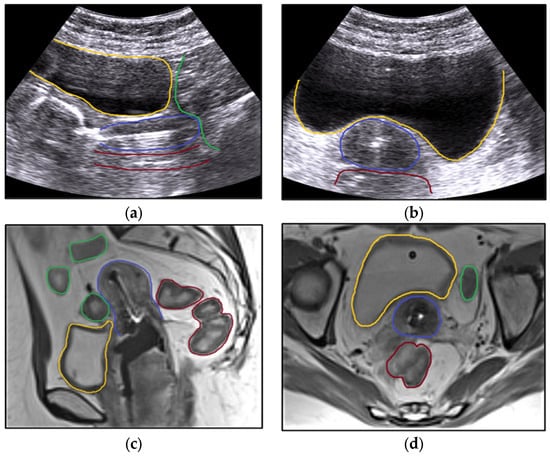

| TAUS | Transabdominal ultrasound |

| TRUS | Transrectal ultrasound |

- Smet, S.; Nesvacil, N.; Knoth, J.; Sturdza, A.; Najjari-Jamal, D.; Jelinek, F.; Kronreif, G.; Pötter, R.; Widder, J.; Kirisits, C.; et al. Hybrid TRUS/CT with optical tracking for target delineation in image-guided adaptive brachytherapy for cervical cancer. Strahlenther. Onkol. 2020, 196, 983–992. [Google Scholar] [CrossRef] [PubMed]

- Nesvacil, N.; Schmid, M.P.; Pötter, R.; Kronreif, G.; Kirisits, C. Combining transrectal ultrasound and CT for image-guided adaptive brachytherapy of cervical cancer: Proof of concept. Brachytherapy 2016, 15, 839–844. [Google Scholar] [CrossRef] [PubMed]